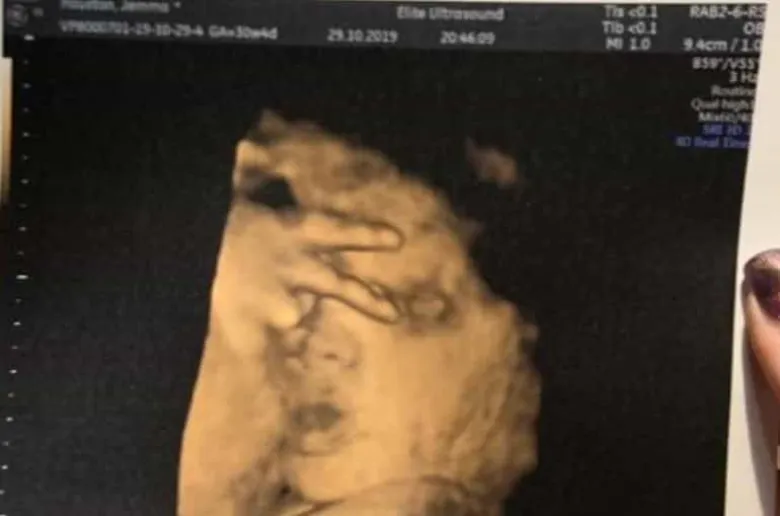

Չծնված երեխան ուլտրաձայնային հետազոտության ժամանակ հաղթանակի՝ «V» նշանն է ցույց տվել՝ ծիծաղեցնելով ծնողներին և ապշեցնելով բժիշկներին, գրում է The Sun-ը:

Շոտլանդիայի Փեյսլի քաղաքի բնակչուհի Ջեմմա Հյուսթոնը պատմել է, որ ուլտրաձայնային հետազոտության ժամանակ իր ապագա երեխան ապշեցրել է բժիշկներին՝ ցույց տալով հաղթանակի «V» նշանը: Հյուսթոնը նշել է, որ իր դուստրն ուլտրաձայնային հետազոտությունների ժամանակ երբեք չի «օգնում» և ճիշտ դիրքում երբեք չի հայտնվում:

Հղի կինը հայտնել է, որ արդեն 4 ուլտրաձայնային հետազոտություն է անցել, սակայն երեխային հստակ ցույց տվող ոչ մի լուսանկար չունի:

Նա հավելել է, որ դուստրն իսկական «դիվա» է լինելու և մորից ժառանգելու է նրա հատկանիշները: Հյուսթոնն ասել է, որ դստեր վարքագիծը շատ ծիծաղելի էր, և նրա լուսանկարն ապագայում անպայման ցույց է տալու նրան: